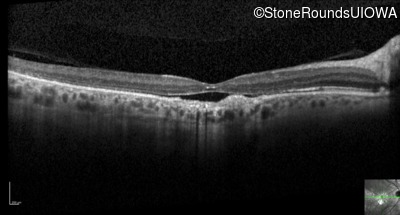

Optical Coherence Tomography - Right - 20/125 -2

Exemplar / OCT Stack